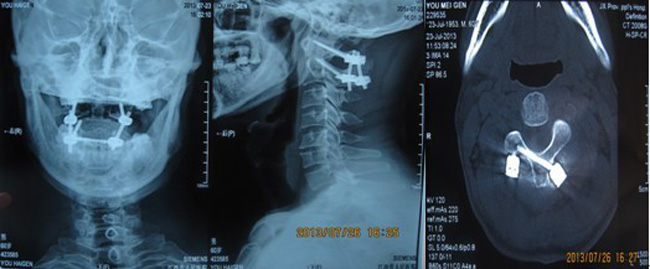

左侧枢椎动脉孔内挤,椎弓根细小 颅骨牵引位下手术

术后寰枢椎复位良好,椎弓根螺钉和椎板螺钉位置精准

齿状突骨折寰椎后脱位不全瘫 枢椎椎动脉畸形,椎弓根极其细小

患者需手术治疗,否则颈脊髓长时间受到脱位的压迫或刺激将导致高位颈髓病甚至瘫痪,而寰枢关节位于脊柱的最高点,作为生命中枢的延脊髓交界从寰枢关节经过,这样的解剖特点使寰枢椎手术有脊柱外科的“珠穆朗玛峰”之称,手术风险高,一旦出现操作失误或并发症,病人就可能高位截瘫,丧失呼吸功能,生命将难以维持。而该例患者还合并椎动脉畸形,术中误伤椎动脉的也是手术的危险因素之一。这样的手术对医生而言无疑是一项挑战。为慎重起见,做到术前心中有数,我多次到双源CT室调阅患者1mm薄层扫描重建CT片,研究椎板螺钉和椎弓根钉技术的可行性, 后提交科室讨论, 最终决定采用目前国内较先进的枢椎椎板螺钉技术(可以避开畸形的椎动脉)结合寰椎椎弓根螺钉技术进行寰枢椎复位固定植骨融合术。随着全麻成功实施,上颅骨牵引,摆体位,显露进针点,植入内固定,复位,取骨植骨,缝合。每一步都有条不紊地进行,每一步都胸有成竹地实施,手术历时3小时,出血约200ml,不用输血顺利完成。术后第4天患者即佩戴颈托下地活动,颈项部疼痛缓解,而术后12天就拆线出院了。